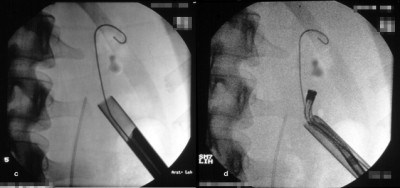

Zur perkutanen Entfernung von Steinen aus dem Nierenbeckenkelchsystem stehen auch flexible Instrumente zur Verfügung (Abbildung 8).

Die Abbildung zeigt das perkutane Vorgehen bei einem Nierenbeckenkelchstein (Abbildung 9).

Bei Anwendung der perkutanen Methoden mit entsprechend miniaturisierten Instrumenten finden sich Steinfreiheitsraten von 58% bzw. bei Entfernung der Reststeine von 81%. Bei zusätzlicher Anwendung von ESWL liegen die Erfolgsraten bei 90% bis 100%